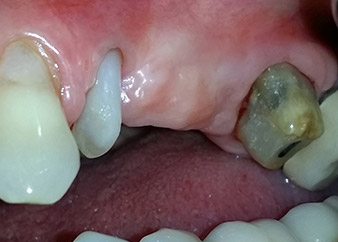

След един месец, в деня на операцията, болката и възпалението в зъб 24 е минимално, но подвижността в Miller class 2 е на лице. След отваряне на ламбата и почистването на периапикалната и перирадикуларната тъкани, обхватът на костния дефект стана очевиден (Фиг. 2 и 3).

В букалния корен, цялата вестибуларна и дистална кост липсва. Захващането е значително ограничено до палатиналния корен, подчертавайки предварително лошата прогноза. Зъб 27 също откри намалено хоризонтално захващане и минимално апикално разреждане (Фиг. 1) без клинични симптоми.

тотална загуба на кост и захват

Фиг. 2 и 3: След повдигане на ламбото, един месец след ендодонтския преглед и прилагане на цялостна периодонтална терапия в цялата уста, букалният корен на зъб 24 разкри тотална загуба на кост и захват.